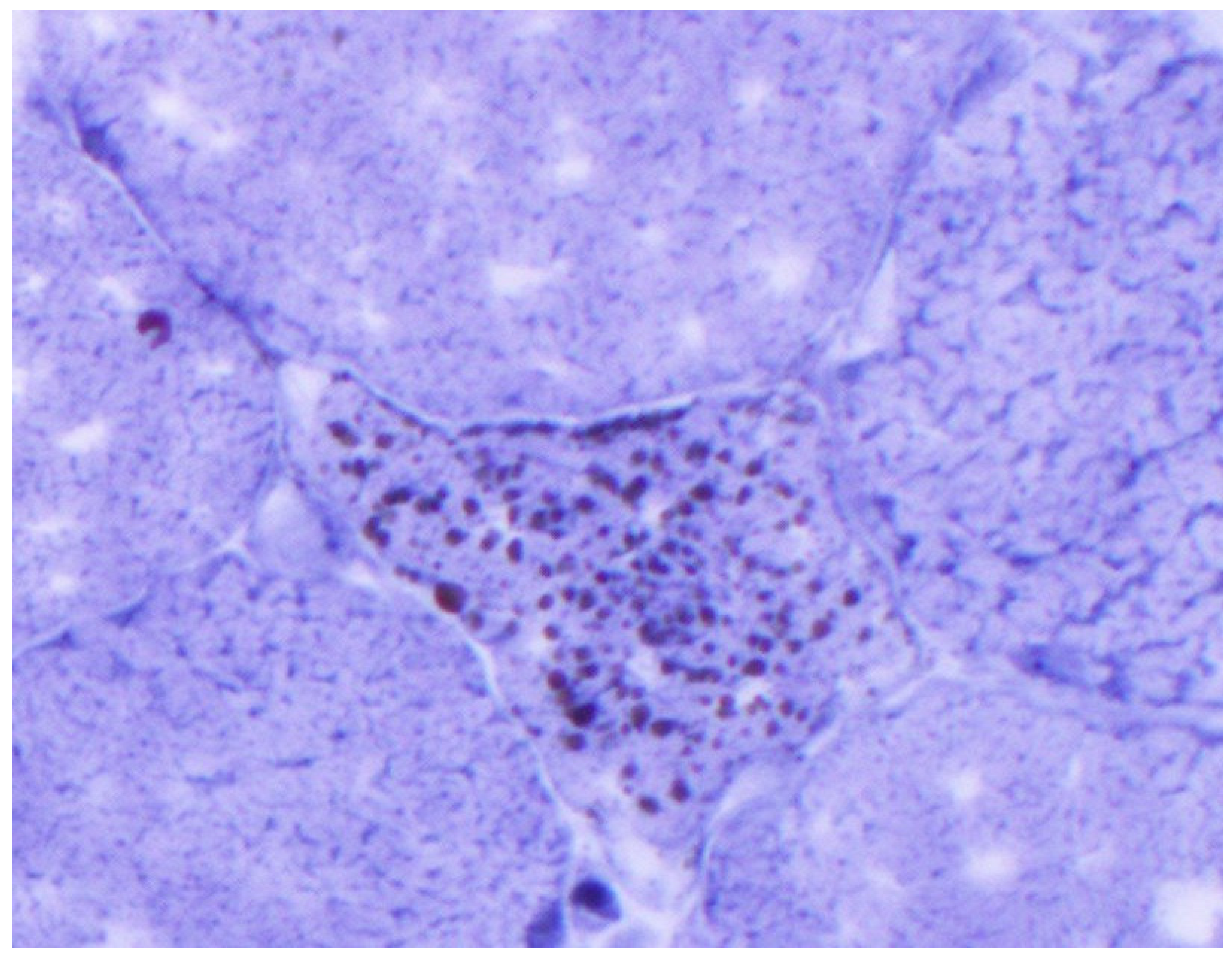

Figure 4.

Sudan black stain: lipid droplets in scattered and intact myofiber (high power).